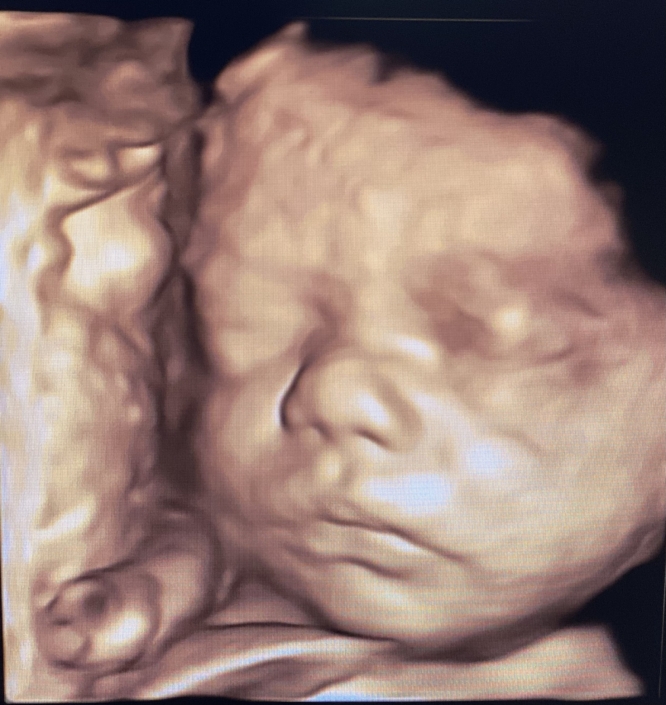

Prenatal Peek®

Prenatal Peek is the leader in 3D 4D Ultrasound. We employ only Certified / Registered Sonographers maintaining unsurpassed standards in 3D ultrasound. You deserve the best! Call us today.